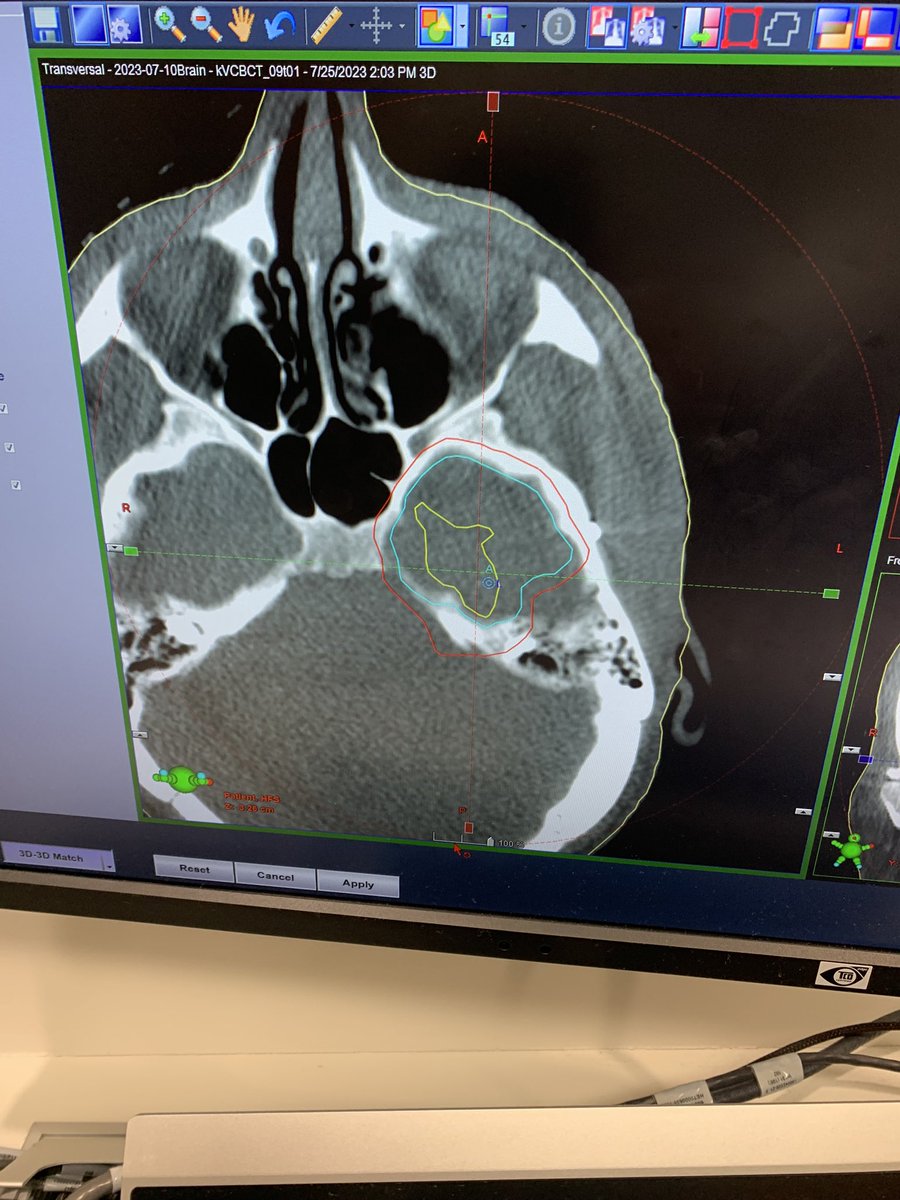

Landmark day 4 me today: half way through daily radiotherapy course (3 weeks to go)! CT scan images mapping my radiotherapy field show how precisely targeted it is (highest dose in yellow circle, less in blue, least in red: like contour lines on a map!).